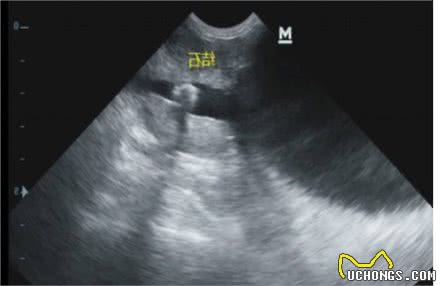

E.B超检查----病犬/猫仰卧保定,腹侧壁和腹底部剃毛,均匀涂抹适量的耦合剂,用探头紧密接触皮肤,在耻骨前缘,横扫时探头以腹中线为轴前后移动,纵扫时探头在耻骨前缘平行腹中线左右移动对膀胱进行扫描。

b超照片。